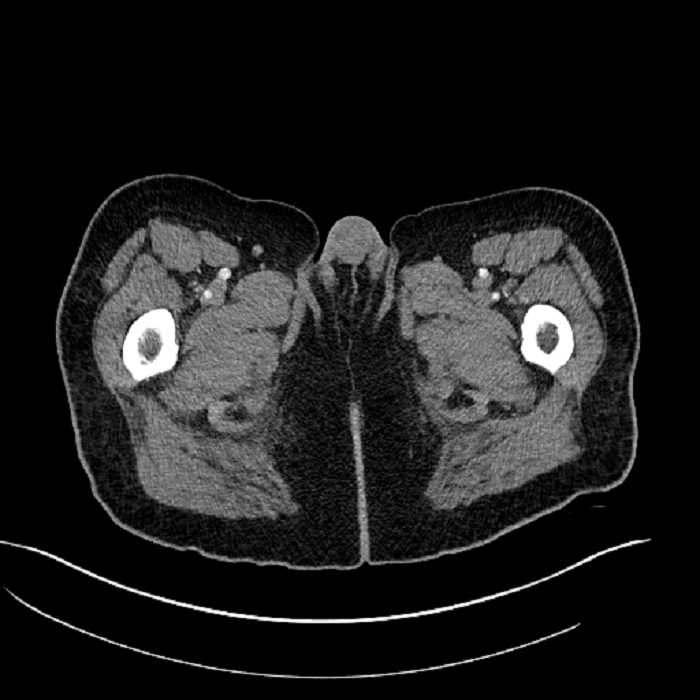

Age: 63

Sex: Male

Indication: Abdominal pain

• Large fluid density structure in hepatic segments 7 and 8 measuring 10 x 7 x 7 cm with internal septation and circumferential ill-defined low density compatible with edema

• Peripherally enhancing subcapsular collections along the anterior margin of the left hepatic lobe measuring 3 x 1 cm and 2 x 1 cm

• Clearly marginated fluid density structure in segment 7 and several other scattered tiny hypodensities, which likely represent cysts

• High grade stenosis of the left common iliac artery, with the left internal and external iliac arteries remaining patent

• Ankylosis of both sacroiliac joints

• Hepatic abscess

Acute sigmoid diverticulitis complicated by a small contained perforation and a large abscess in the right hepatic lobe. Additional small subcapsular abscesses along the anterior margin of the left hepatic lobe.

Additionally, loss of the normal fat plane between the peridiverticular collection and adjacent thickened loops of small bowel raises the potential for an enterocolonic fistula.

High grade stenosis of the left common iliac artery. The left external and internal iliac arteries are patent.

Hepatic abscess showing the double target sign with low density internally surrounded by a thin inner enhancing rim (red arrow) and ill-defined outer low density rim (yellow arrow). Blue arrow indicates an internal septation. Red arrows: additional smaller subcapsular abscesses. Red arrow: focal contained perforation associated with diverticulitis.